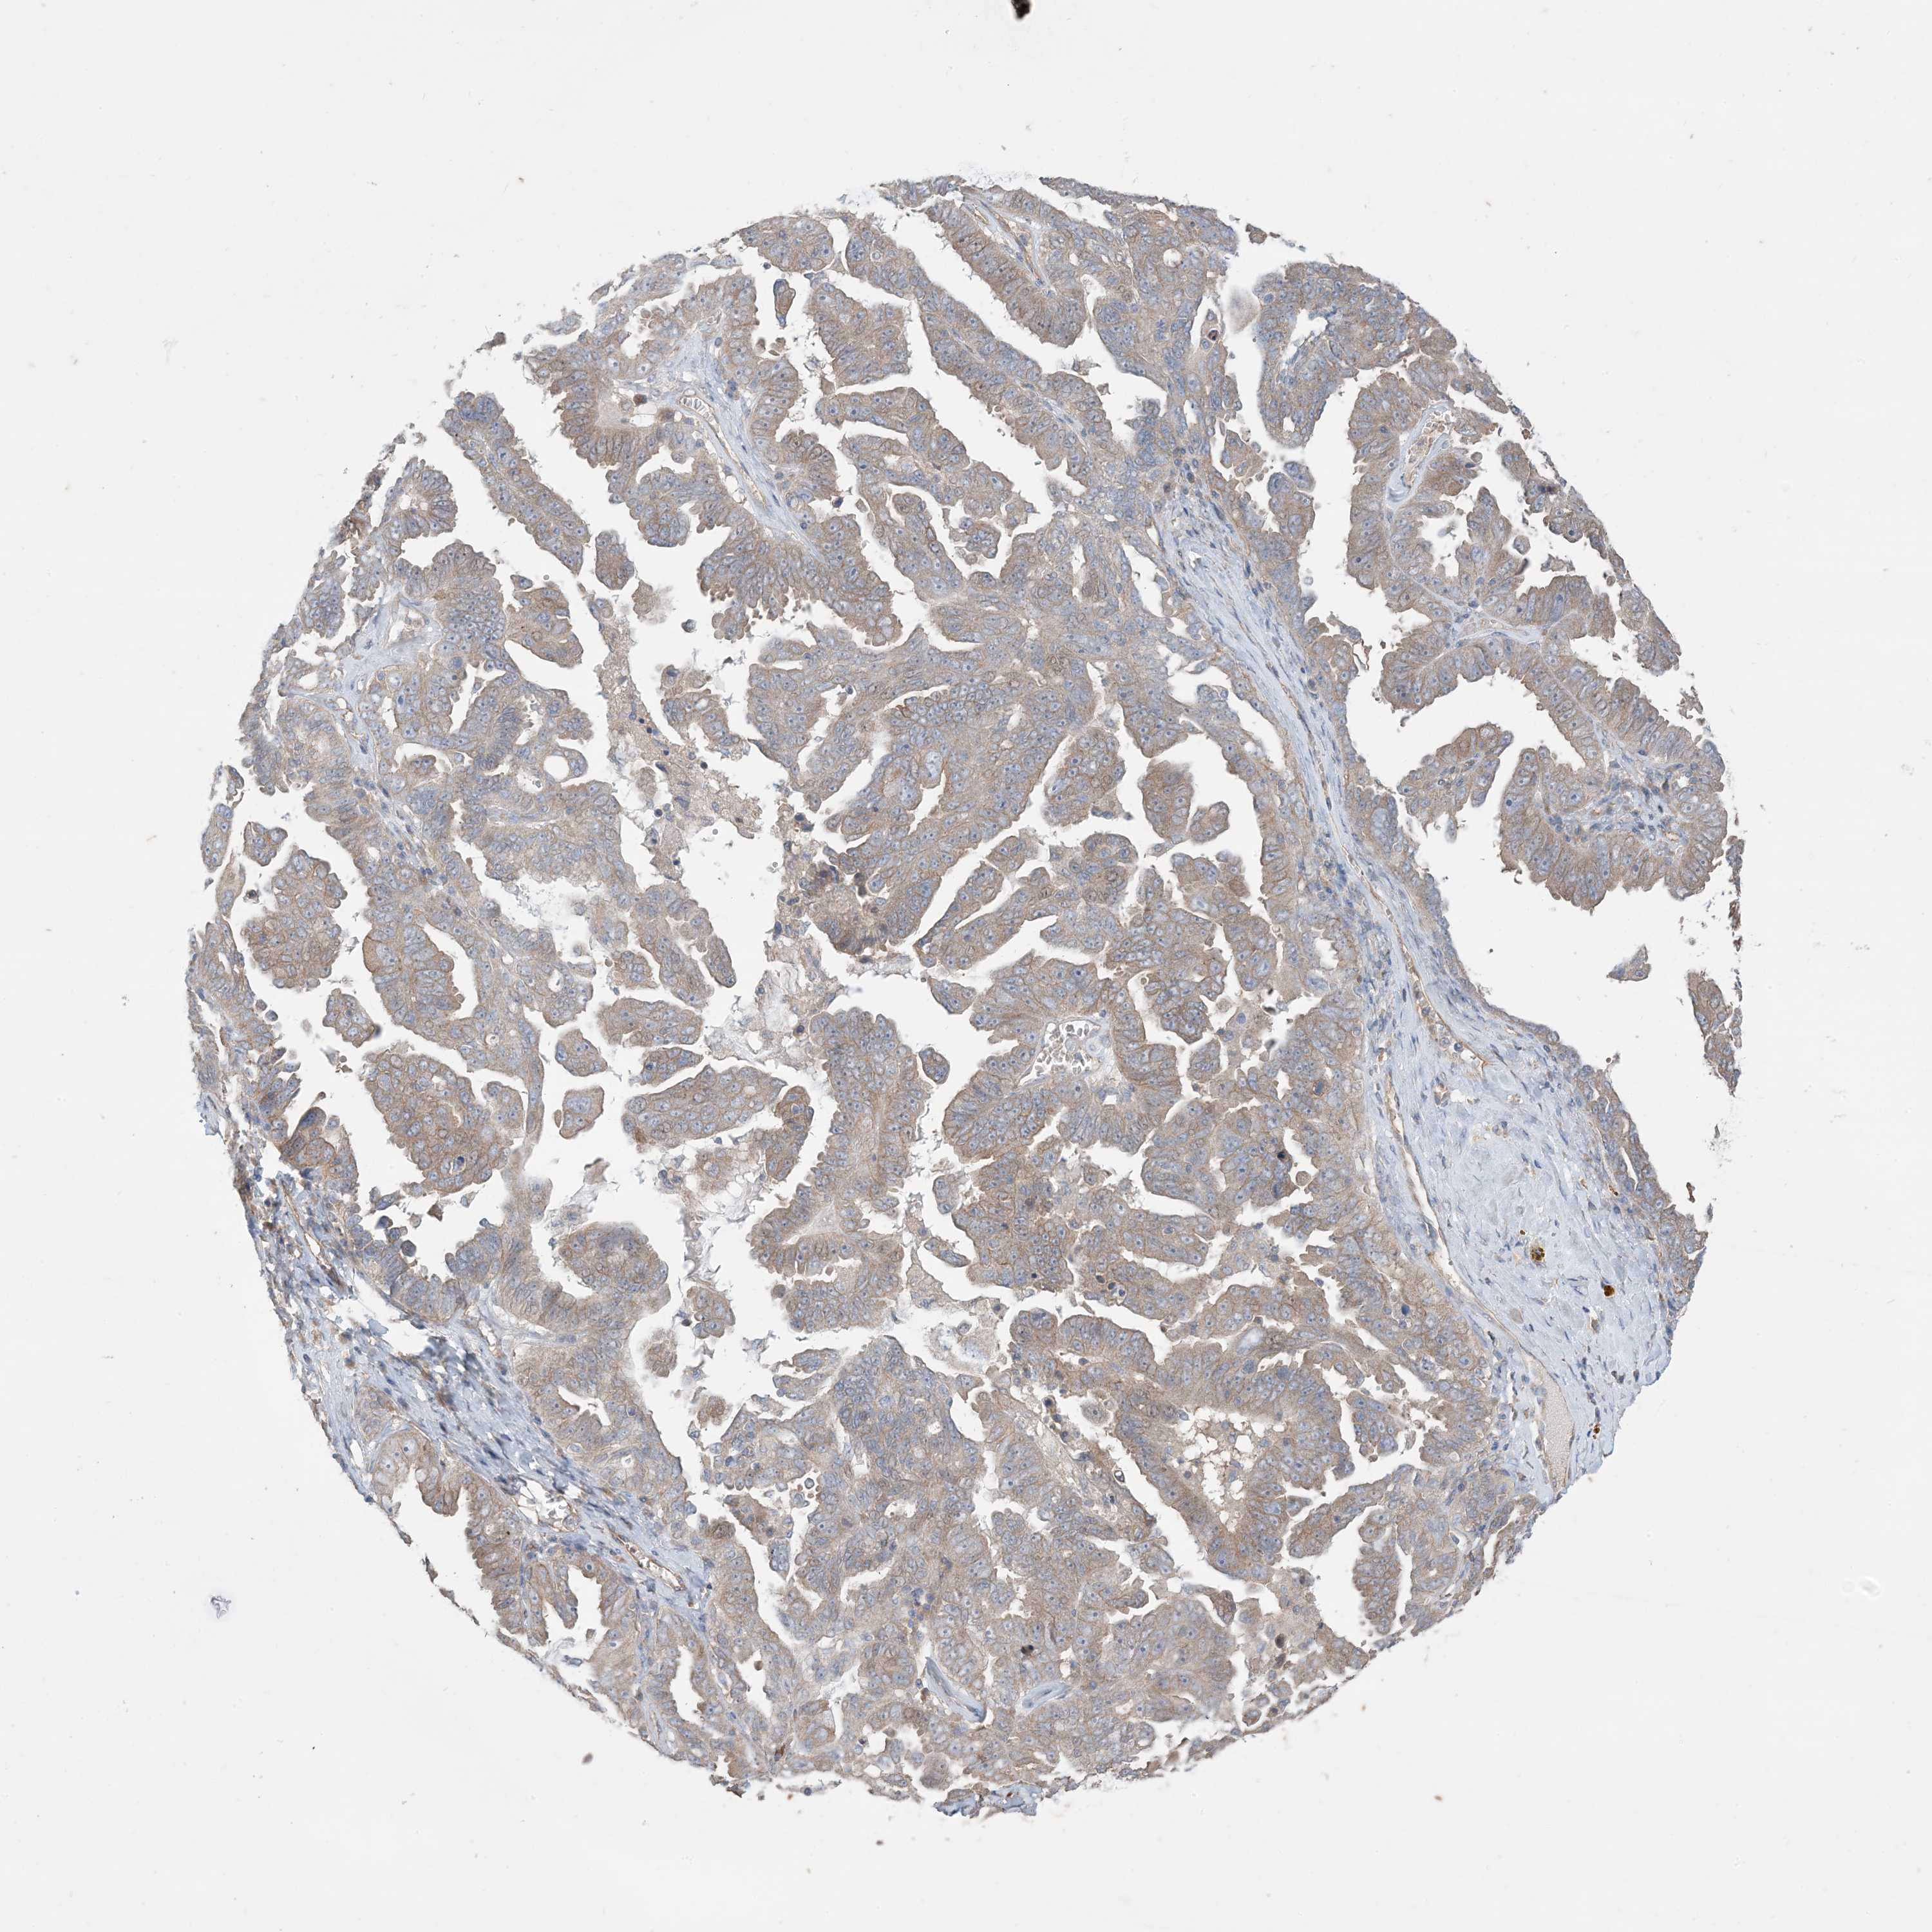

OVARIAN CANCER - Protein expressioni

A mouse-over function shows sample information and annotation data. Click on an image to view it in a full screen mode. Samples can be filtered based on level of antibody staining by selecting one or several of the following categories: high, medium, low and not detected. The assay and annotation is described here.

Note that samples used for immunohistochemistry by the Human Protein Atlas do not correspond to samples in the TCGA dataset.

Antibody stainingi

Antibody staining in the annotated cell types in the current human tissue is reported as not detected, low, medium, or high, based on conventional immunohistochemistry profiling in selected tissues. This score is based on the combination of the staining intensity and fraction of stained cells.

Each image is clickable and will lead to virtual microscopy that enables deeper exploration of all samples and also displays staining intensity scores, fraction scores and subcellular localization as well as patient and tissue information for each sample.

Antibody HPA036290

Staining

High

Medium

Low

Not detected

Intensity

Strong

Moderate

Weak

Negative

Quantity

>75%

75%-25%

<25%

None

Location

Nuclear

Cytoplasmic/membranous

Cytoplasmic/membranous,nuclear

Cystadenocarcinoma, serous, NOS

Carcinoma, endometroid

Cystadenocarcinoma, mucinous, NOS

Carcinoma, NOS